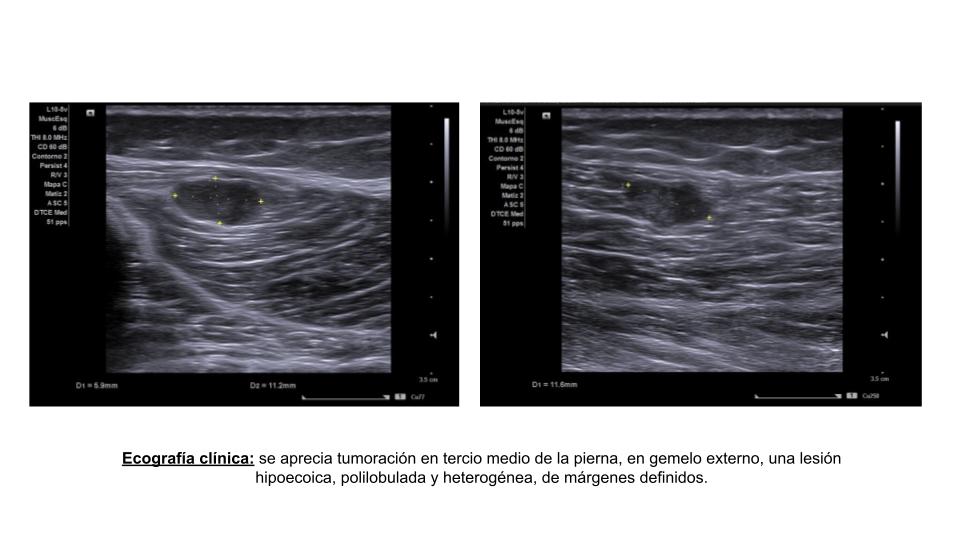

En ecografía clínica se aprecia en tercio medio de la pierna, en gemelo externo, una lesión hipoecoica, polilobulada y heterogénea, de márgenes definidos, con flujo Doppler central y periférico, de 1,7 x 5,8 x 11,6 mm.